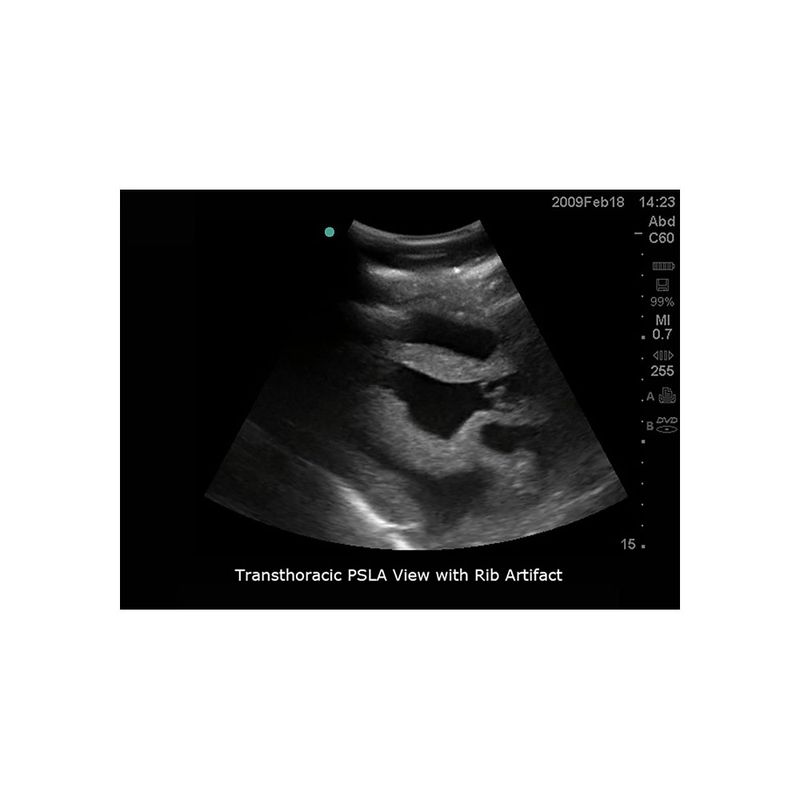

模型具有精准的内外部解剖结构,能与任何带经食道超声探头、心脏探头及腹部探头的超声影像检查设备联合使用,可进行经食道超声心动图(TEE)、经胸廓心超声心动图(TTE)、超声引导下心包穿刺术等完整操作流程训练。适合于心血管内科、急诊科、重症医学科、超声科等学科使用。